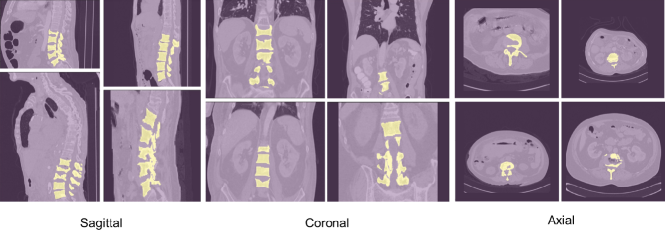

The VerSe2020 dataset consists of 319 CT scans and approximately 300 patients with a mean age of 59(±17) years participated to collect the dataset. The scans are split into 113, 103, and 103 for training, validation, and test set, respectively. The total number of vertebrae is 4141 in which cervical (CER) make up 581, thoracic (THO) consists of 2255, and lumbar (LUM) number is 1305. The dataset provides 3D data that we used 2D view sagittal and coronal planes for segmentation. Some samples of VerSe2020 dataset from sagittal, coronal and axial views are illustrated in Figure 1.